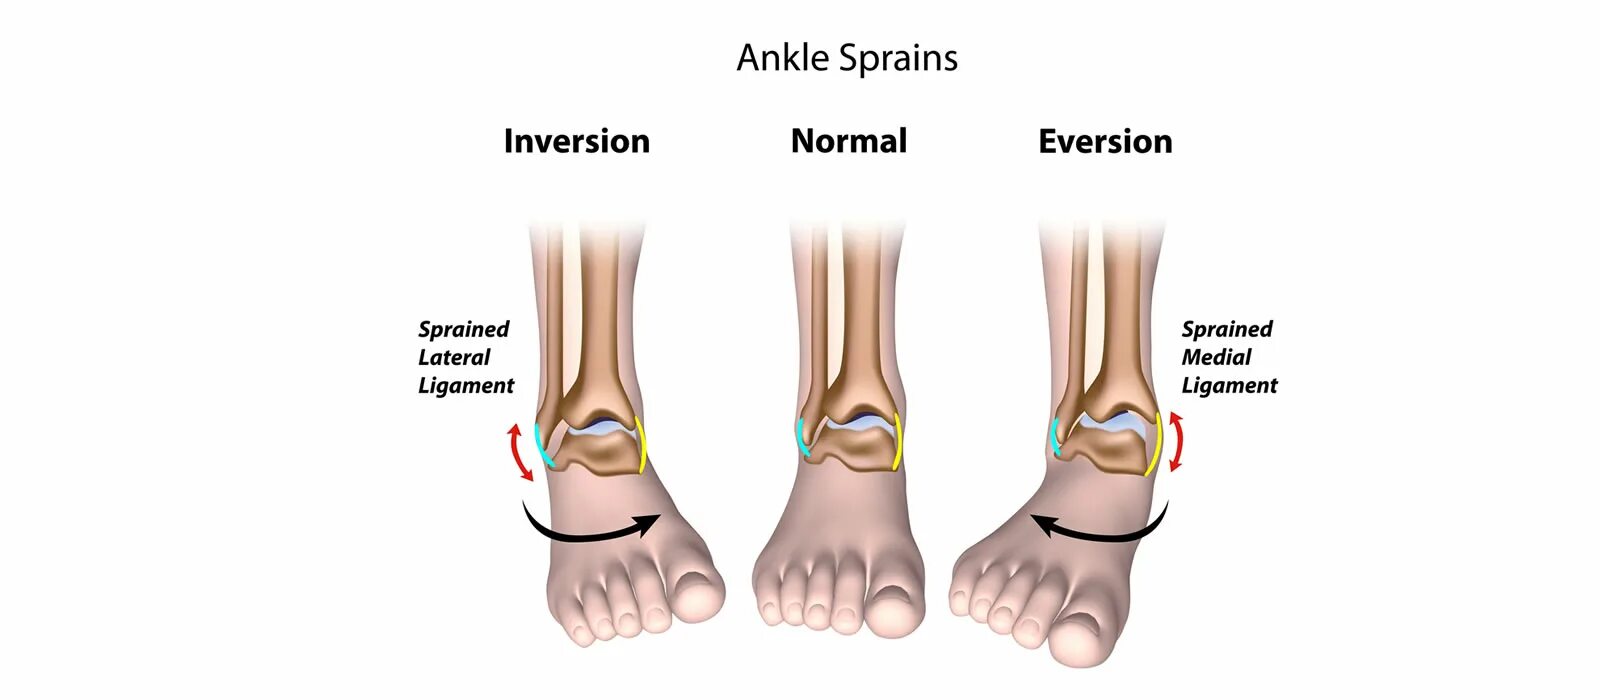

Растяжение связок голеностопа как долго